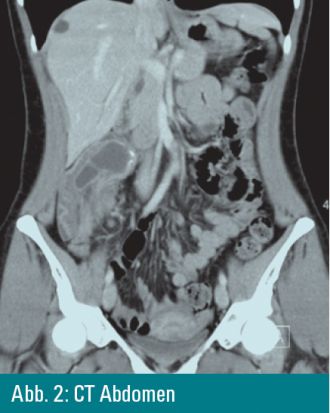

Mittelbauch eine kindskopfgroße Resistenz tastbar. Die CT-Untersuchung

des Abdomens diagnostiziert einen teilweise verkalkten Tumor, der in das

Colon aszendens vaginiert ist, mit pathologisch vergrößerten

mesenterialen Lymphknoten. Die angeschlossene Ultraschalluntersuchung